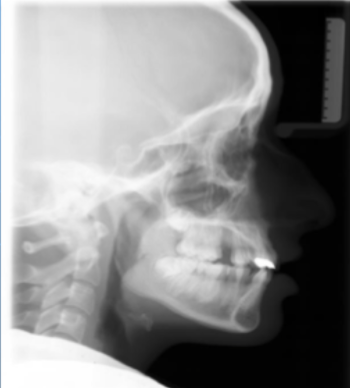

7

Q

name this extra-oral radiograph

A

Lateral cephalogram